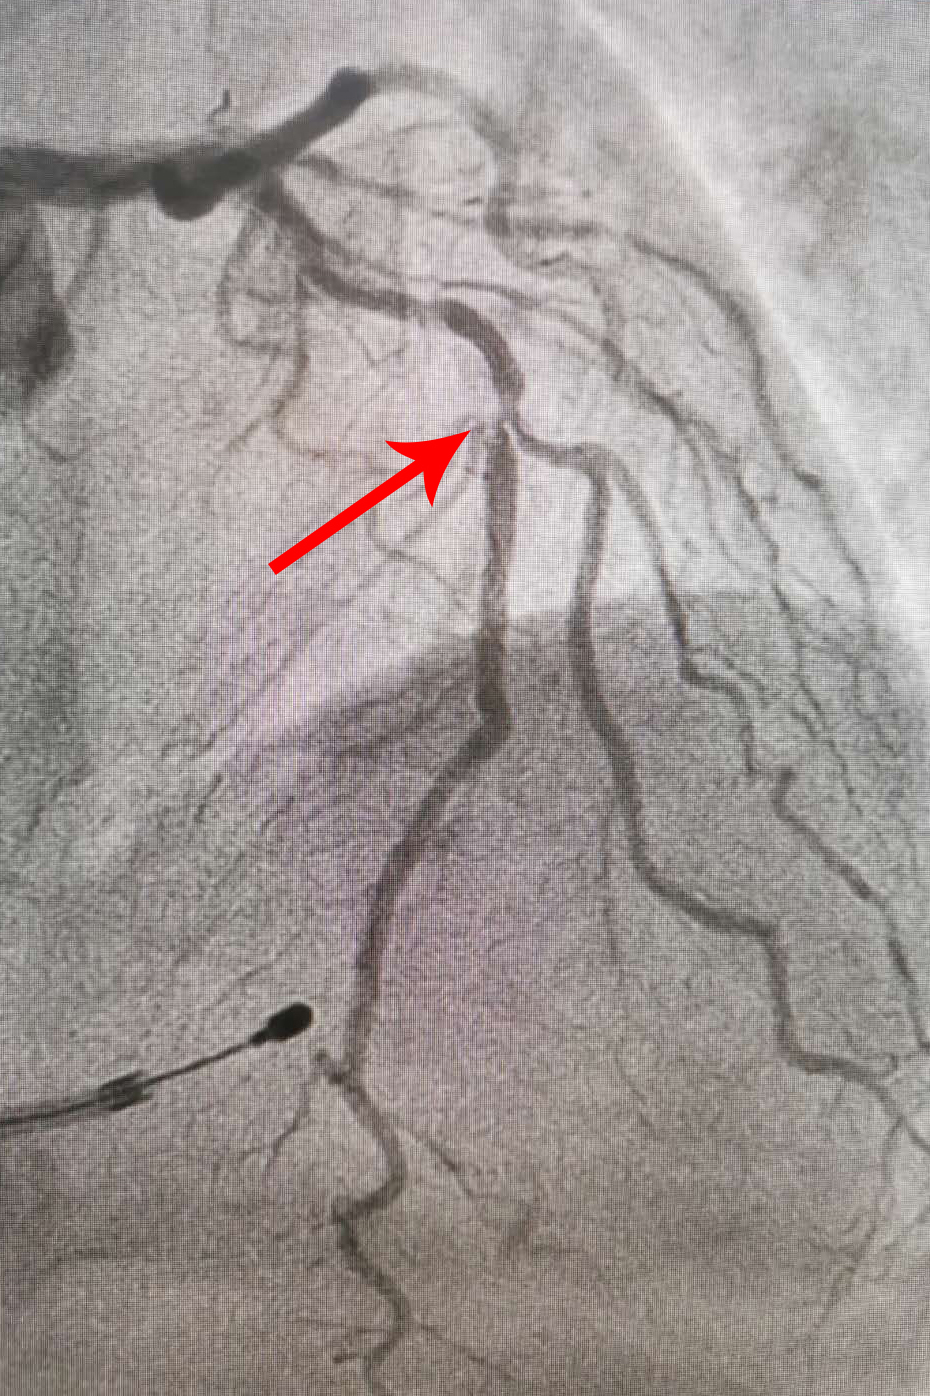

冠脈支架植入后

主動脈瓣植入后